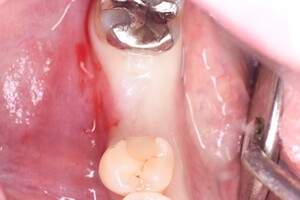

インプラント治療の症例1

レントゲン写真

- 透過像

症例写真-1

- Befor

- After

症例写真-2

- 途中経過

| 年齢 | 50代・男性 |

| 主訴 | 右下歯が疼く |

| 治療内容 | ・右下6番インプラント ※1:FGG(遊離歯肉移植術)とは、足りない歯ぐきを上顎から上皮を切り取り移植する外科手術 |

| 治療費 | 合計:902,000円(税込) ■内訳 |

| 治療期間 | 9ヵ月 |

| 治療方針 | 右下の当該歯は歯根破折により保存不可能と診断しました。歯周疾患も伴っていたため抜歯後に骨吸収※1が大きく起こることが予測できました。チタンメッシュ併用骨再生誘導法(GBR※2)を選択しインプラント埋入と同時に行い自然な歯槽骨のラインを再現しました。またGBRを行う際にインプラント辺縁の付着歯肉の減少が起こる為、遊離歯肉移植術(FGG※3)を行い清掃性を考慮した形態に仕上げました。 ■治療方針の解説 治療した右下の歯をレントゲンで撮影したところ根本の部分に黒く写る箇所があり「根尖性慢性周囲炎※1」と診断。また歯周病も進行していました。 ※1 骨吸収・・・歯槽骨という歯を支える骨がなくなっていくこと |

| 担当者所見 | 主訴の右下だけでなく歯茎の腫れ、発赤があり不良補綴や不良充填など他にも治療箇所が多数ありました。プラークコントロールが不良であった為まずはブラッシング指導を行いセルフケアの重要性を理解していただくところからスタートしました。 右下6番の歯はインプラント治療を行なった結果審美的にも機能的にも患者様の満足を得ることができました。骨造成と歯肉移植も行なった為インプラントを支える十分な歯周組織の獲得ができたと思っております。 |